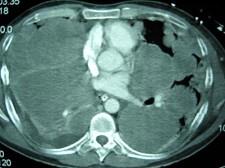

问题 33岁,男,咳嗽1周,有骨肉瘤病史,请结合胸片和CT选出最可能的诊断 ( )

选项 A、结节病 B、错构瘤 C、粟粒性肺结核 D、骨肉瘤转移 E、肺梗死

答案 D